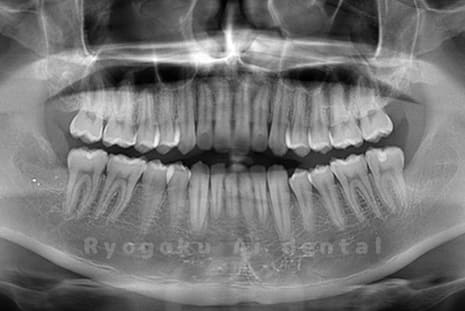

水平埋伏の親知らず

歯茎の中で完全に横に生えてしまうタイプです。

この親知らずを水平埋伏智歯と言います。このタイプはほとんどが下顎のケースです。真横に生えているので抜歯の際は難易度が高く2~3つに砕いて分けて抜歯をします。